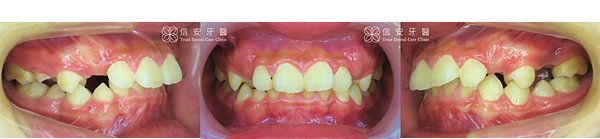

▲Tony的上門牙向前暴出,有嚴重深咬現象,也導致上顎較突出,下顎後縮。

▲Tony屬於第二級咬合不正,合併有深咬、暴牙、牙齒擁擠等問題。

▲可以看出Tony在矯正之後,暴牙明顯往內推,矯正過程也預留恆齒的生長空間。

▲隱適美MA可以做到擴弓、引導顎骨生長的效果。